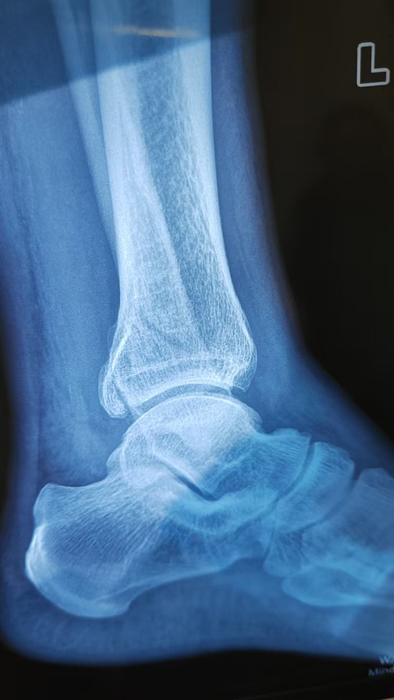

2月4日,何店鎮(zhèn)中心衛(wèi)生院接診一名左踝關(guān)節(jié)外傷患者,經(jīng)影像檢查,確診為左脛、腓骨下段骨折。外科醫(yī)生姜穩(wěn)迅速完成術(shù)前檢查及病情評(píng)估,并與患者及家屬深入溝通治療方案。在患者強(qiáng)烈要求于本院進(jìn)行手術(shù)的情況下,為最大限度保障手術(shù)質(zhì)量與安全,該院特邀請醫(yī)共體牽頭單位——曾都區(qū)人民醫(yī)院脊柱創(chuàng)傷外科專家團(tuán)隊(duì)前來指導(dǎo)。